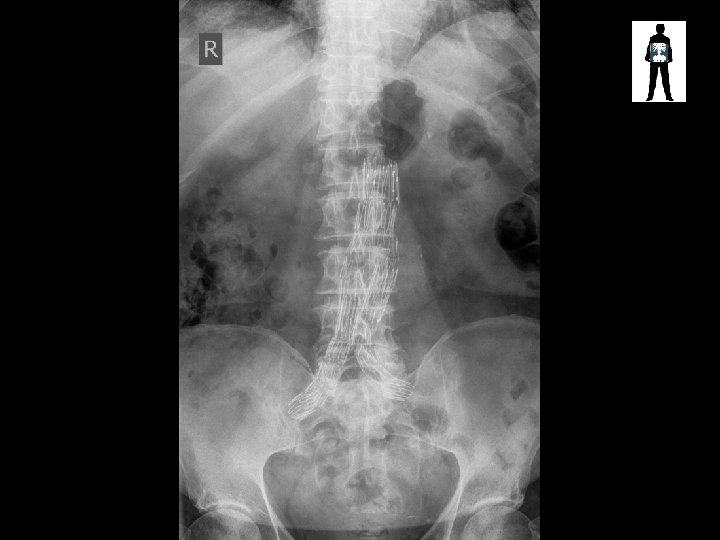

VASCULAR STENT

Aortic Stent • Used to treat aneurysm • Deployed when aneurysms are not near arteries that could be occluded (renal, etc)